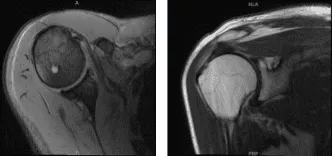

El paciente presentó resultados de resonancia magnética que mostraron tendinosis del manguito rotador, más pronunciada en el tendón supraespinoso, donde una ruptura de grosor total en la parte central de la inserción mide 8 mm y hay una ruptura parcial de bajo espesor articular que se extiende más proximalmente hacia la zona crítica.

Tendinosis infraespinosa leve a moderada con una pequeña rotura superficial del costado articular. Pequeño desgarro no desplazado en el labrum superior. Pequeño encondroma dentro de la cabeza humeral.

Resonancia magnética Hombro derecho sin contraste